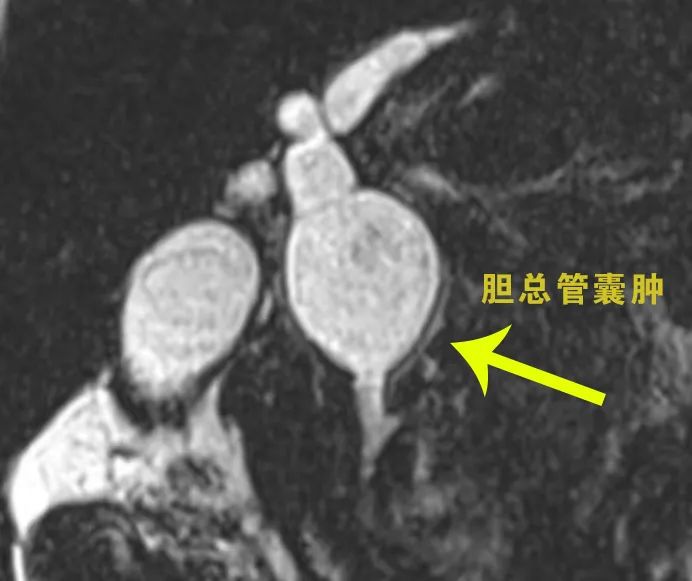

24岁宋女士,在8年前被诊断为“胆总管囊肿”。近日,她因腹痛、腹胀、发热到我院肝胆外科就诊,被初步诊断为胆总管囊肿、胆总管结石、急性胰腺炎,而且她的腹腔出现了积液。

结合宋女士的病情,刘兴贵、杨波组织科室团队详细讨论,经过全面评估,决定施行手术治疗。手术可采取腹腔镜胆道外引流或腹腔镜胆总管囊肿切除、胆肠吻合术;如果仅行胆道引流,患者后期还需要再行一次手术。

一切准备就绪后,刘兴贵、杨波及科室团队为宋女士行腹腔镜胆总管囊肿切除术+胆肠吻合术。术中同时清除了胆总管结石和腹腔积液,一次手术解决了多个问题。为此,宋女士还在自己的社交账号上分享了自己的经历。